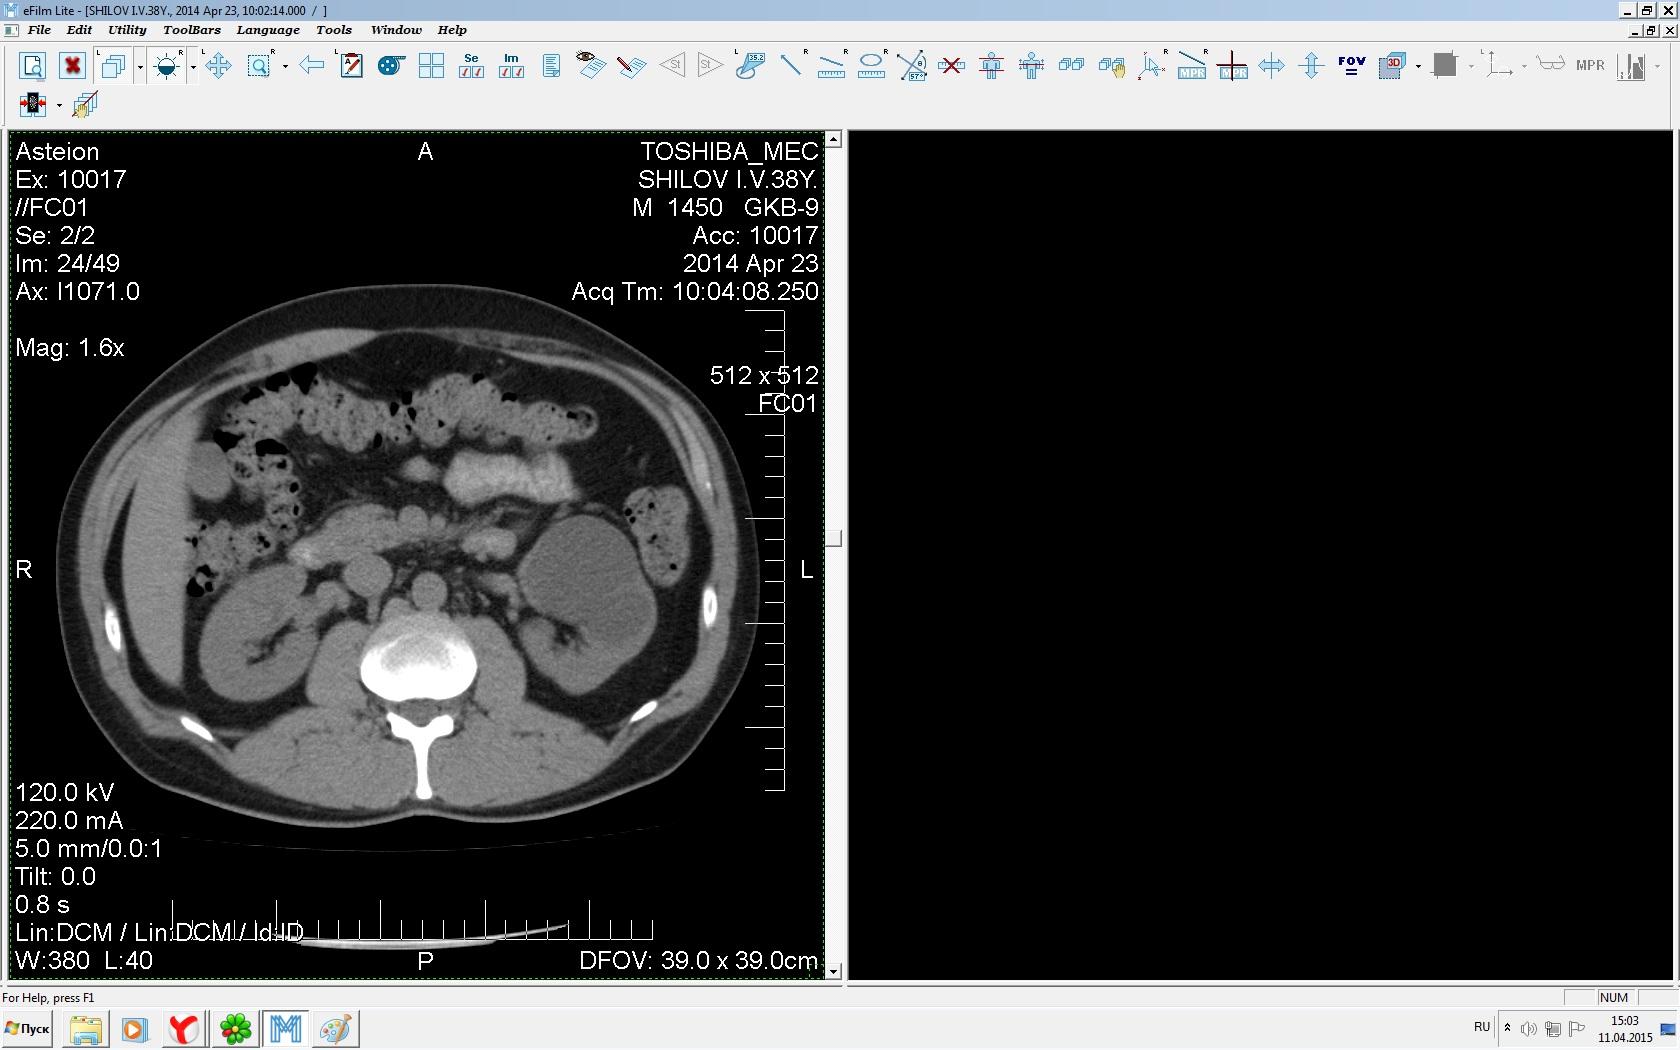

Здравствуйте. У меня киста левой почки. Из заключения: левая почка увеличена, деформирована за счёт наличия в среднем сегменте округлого жидкостного +6, +15 HU образования 66х53 мм, деформирует, поддавливает чаше-лоханочную систему. Сосудистые ножки структурные. В урологии мне сперва предложили лапароскопию, когда я лёг на операцию - изменили на полостную в связи со сложностью. Потом сказали что шансов вырезать кисту без почки практически нет. Даже если кисту удалить чудесным способом, то почка всё равно сложится и не будет работать. В итоге операцию отменили. Скажите, пожалуйста, есть ли современный метод удалить кисту и сохранить почку в моём случае? Томография почки в приложениях. Заранее благодарю.

Эту кисту можно просто пропунктировать, аспирировать и склерозировать - под местной анестезией. Ничего сверхестетственного не определяется по данным КТ. Можете написать мне на почту. aristova-tatyana@mail.ru